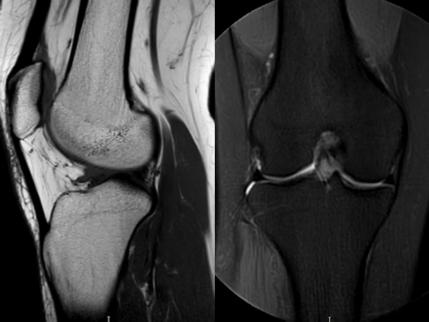

1. “咯吱響”+“卡頓感”——半月板的“碎玻璃警報”

場景:下蹲時膝蓋“咯噔”彈響,起身像被“卡住”

MRI偵查:精準捕捉半月板撕裂或變性(半月板內(nèi)高信號),避免拖成“關(guān)節(jié)交鎖”

(半月板撕裂)